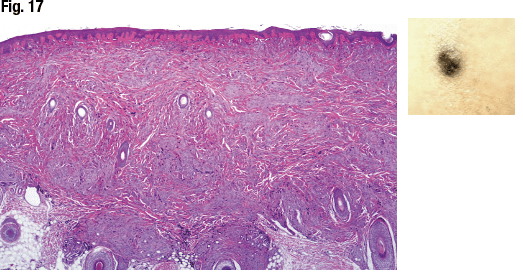

She presented the case of a 19-year-old male with a pigmented nodule on his scalp. Large hypercellular melanocytic proliferation with uniform pigmentation is seen in Fig. 17 and elongation of rete ridges and small junctional component of the melanocytic proliferations in Fig. 18. “We found some of the cells showed very small nucleoli,” Dr. Aung said (Fig. 19). Ki67 staining showed a low to absent proliferative rate. HMB-45 showed diffuse positivity.